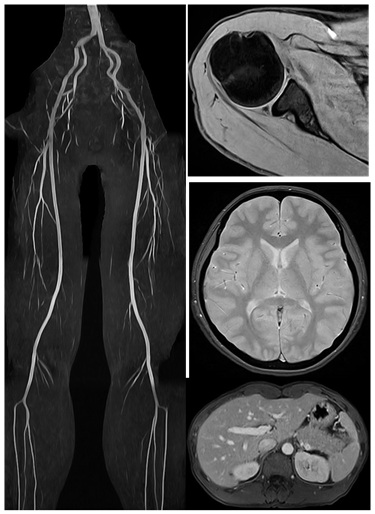

医療現場で日々使われているMRIですが、実はその画像には物理的な原理や撮像条件によって さまざまな“クセ”が現れることがあります。例えば、同じ組織でも撮影法によってまるで違う ように見えることがあったり、当たり前のように毎日見ている画像の裏には、様々なトレードオフの関係があるんです。

そんなMRIの奥深い世界を専門的すぎず、なるべくわかりやすく解説していきます。また、当クリニックで撮像した画像を提示しながら診療放射線技師の方や医学生、放射線科以外の画像診断に興味のある医師の先生方はもちろん、医療に関心のある一般の方にも楽しんでいただける内容を目指していきます。

皆さんがもしMRI検査を受けることになったら、「どこで検査しても同じでしょ?」と思っていませんか?実はこれ、大きな誤解なんです。MRIの画像診断の質は、装置の「性能」によって大きく左右されるんです。

この強度が高いほど、空間分解能が向上し、まるで高性能なズームレンズのように、体の中の微細な構造や小さな病変をよりクッキリと映し出すことができます。

スルーレイトが高いと、まるでシャッタースピードの速いカメラのように、撮影時間が短縮されるだけでなく、体の動きによるブレ(モーションアーチファクト)を抑え、より鮮明な画像を取得することが可能になります。

早期発見の可能性向上:小さな病変や微細な異常も見つけやすくなります。

検査時間の短縮:高性能なほど効率的に撮影でき、患者さんの負担も軽減されます。